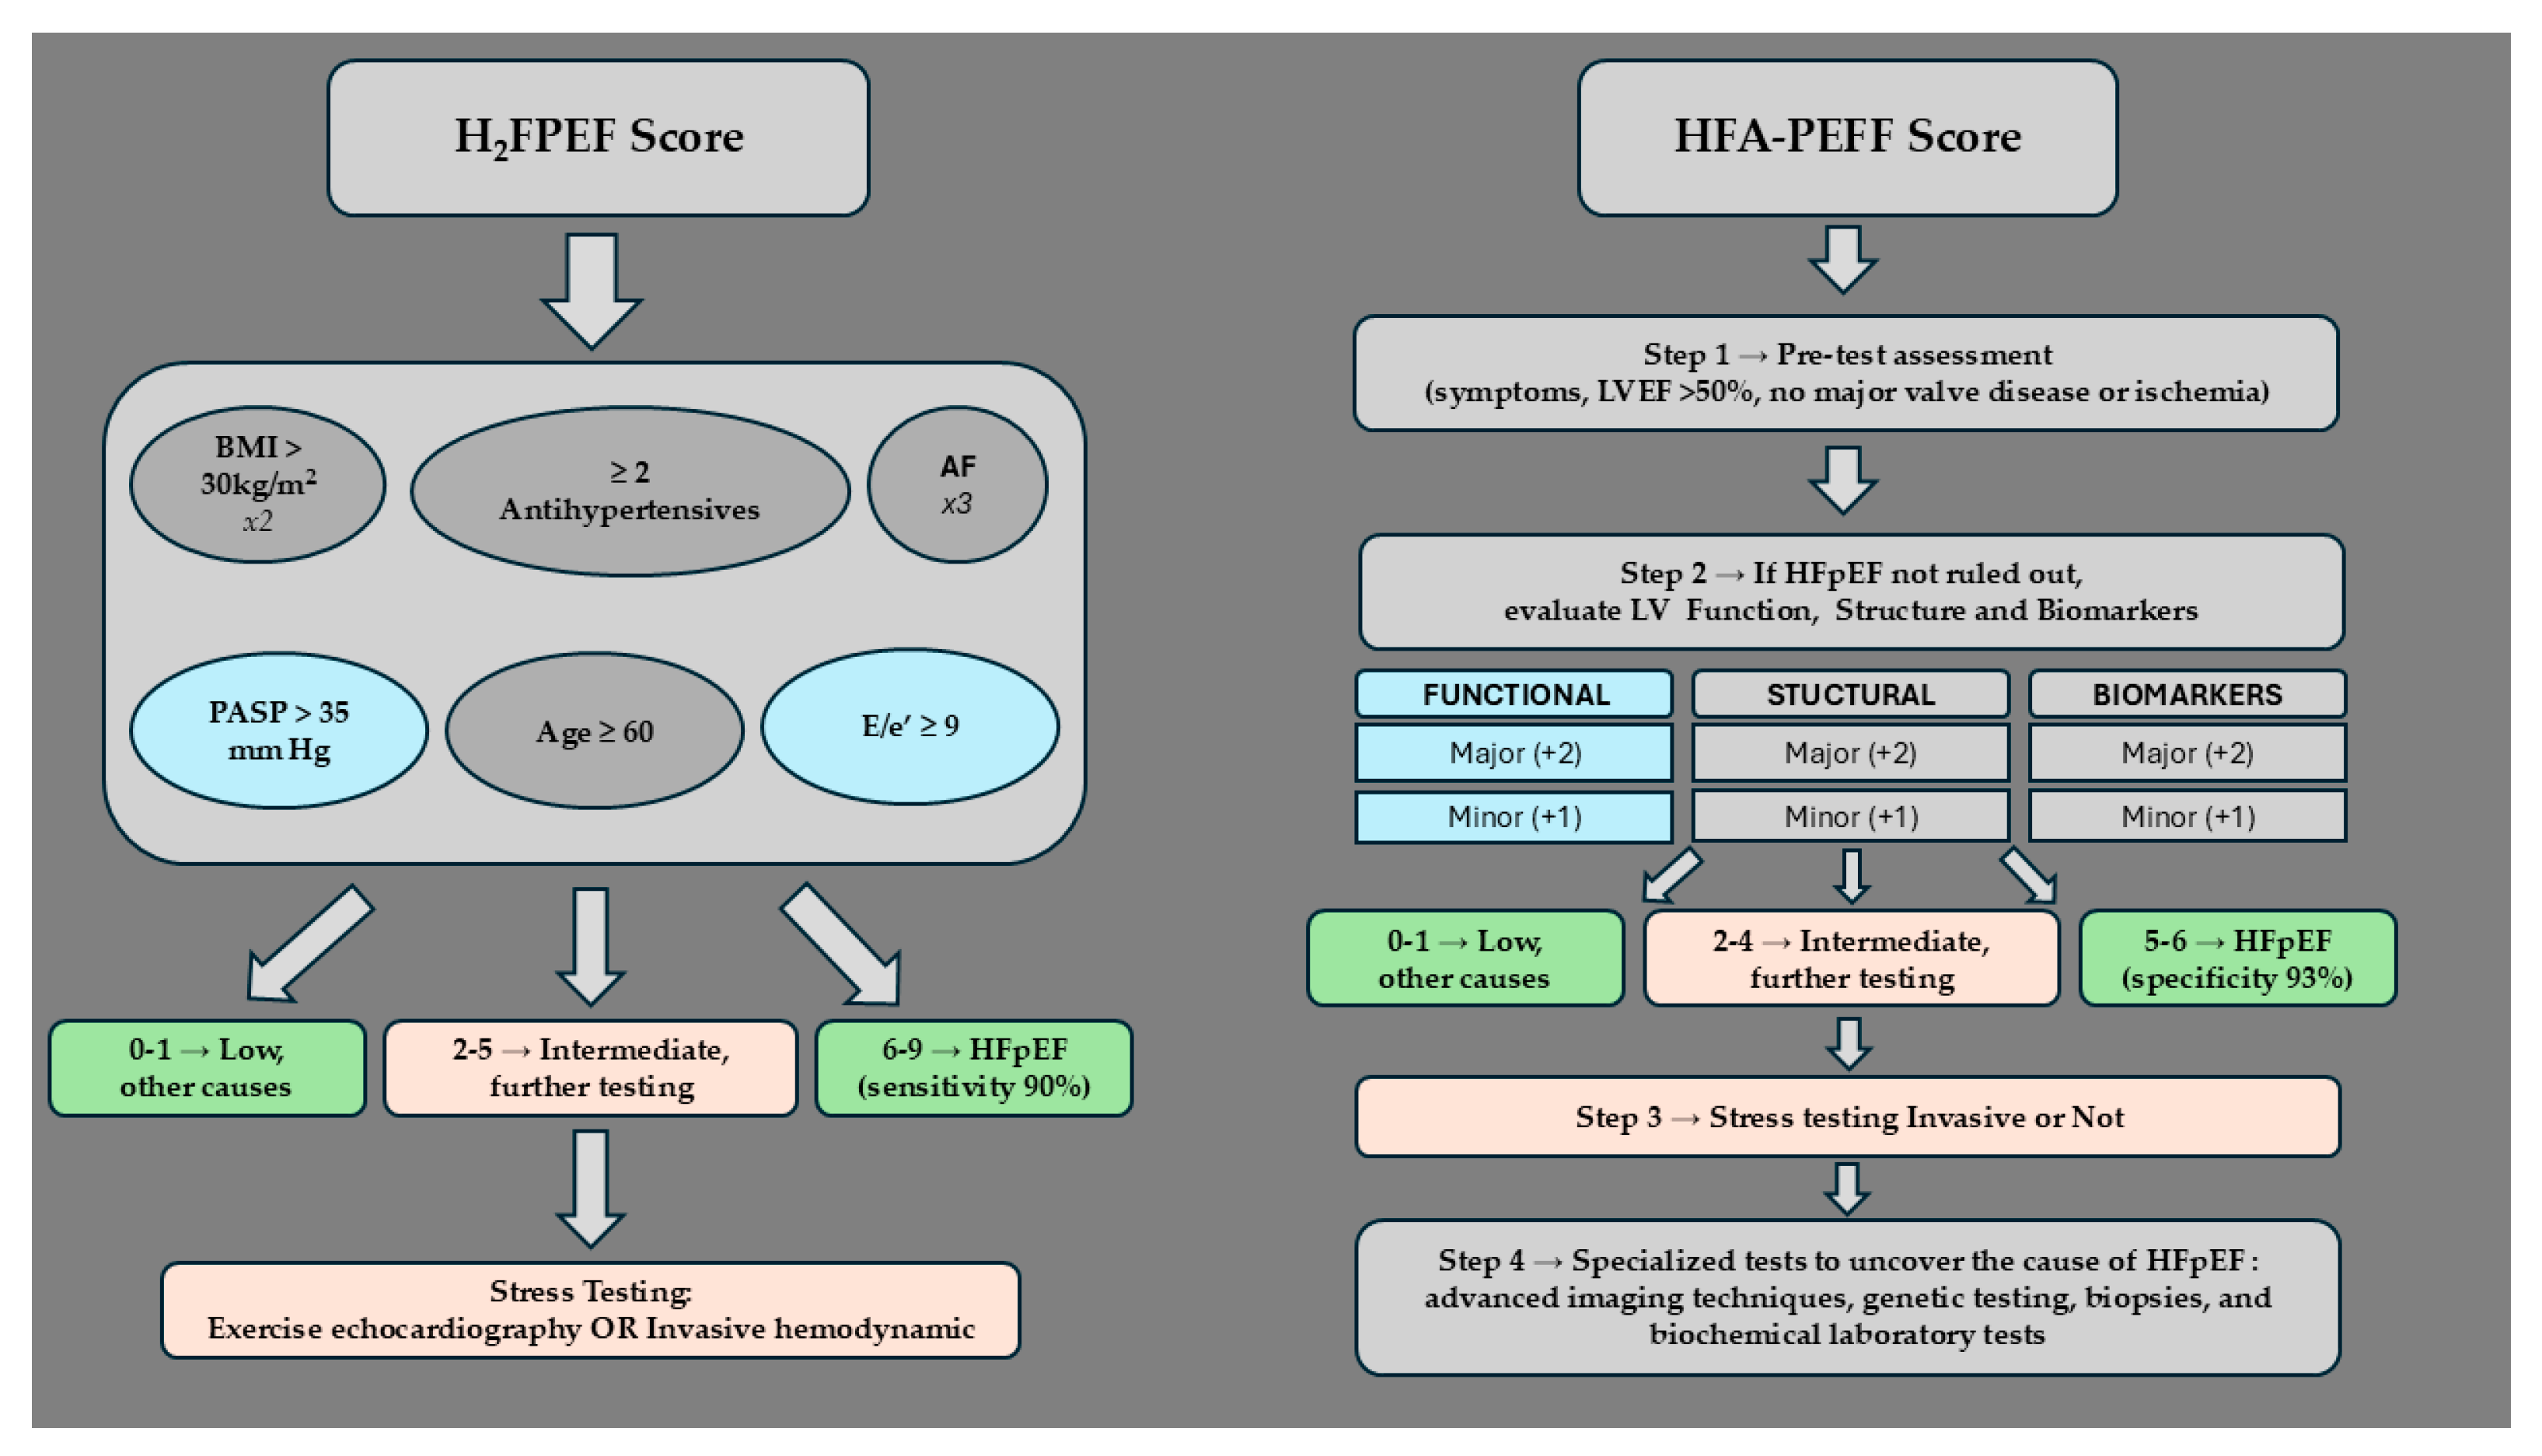

7. Applying Clinical Algorithms in Patients Who Are Obese for HFpEF Diagnosis

7.1. H2FPEF Diagnostic Algorithm

7.2. HFA-PEFF Diagnostic Algorithm

7.3. Accuracy and Limitations of the Diagnostic Algorithms